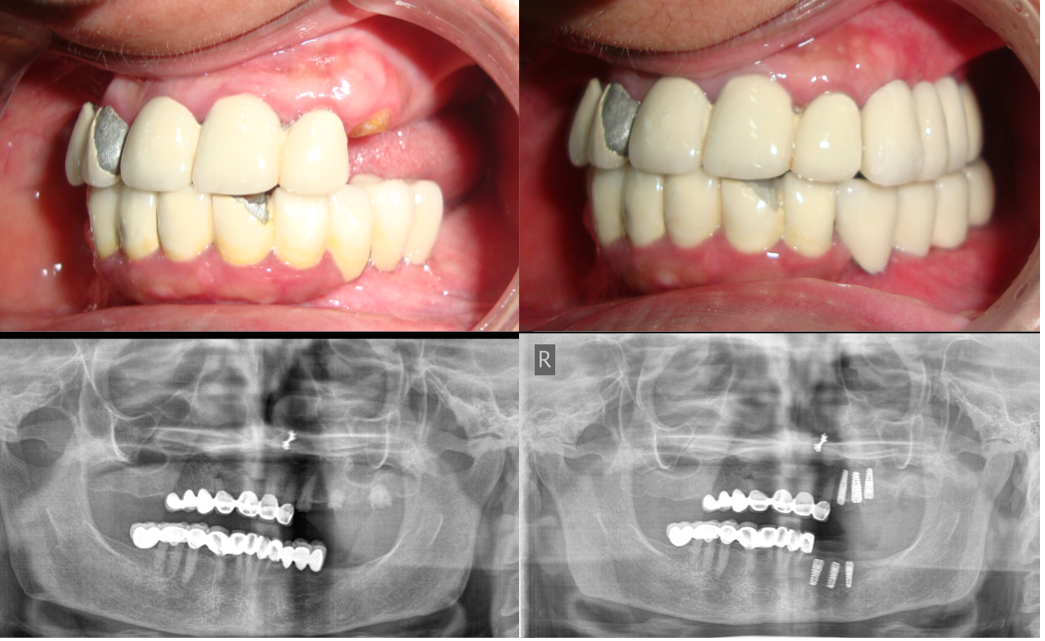

Full Mouth Rehabilitation

Card image